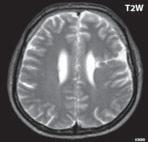

Obr. I.1.1f Rozšířené subarachnoidální prostory (věk 6 měsíců – v tomto období se nejedná o patologický stav, ale jsou fyziologicky prostornější)

Obr. I.1.1g Rozšířené subarachnoidální prostory (věk 6 měsíců – v tomto období se nejedná o patologický stav, ale jsou fyziologicky prostornější); stejný pacient jako na obr I 1 1f

f g h ch

Obr. I.1.1h Fyziologický nález, již normální šíře subarachnoidálních prostor (věk 1,5 roku); stejný pacient jako na obr I 1 1f, g

Obr. I.1.1ch Fyziologický nález, již normální šíře subarachnoidálních prostor (věk 1,5 roku); stejný pacient jako na obr I 1 1f, g, h